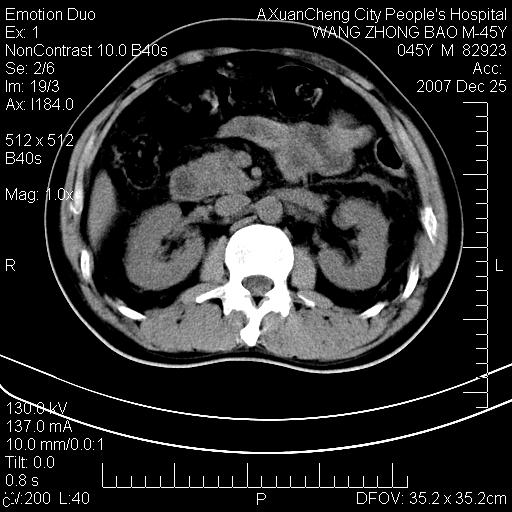

以下是引用qiuleiyu在2007-12-25 18:14:00的发言:[br]胰腺增大,周边渗出改变,肾前筋膜明显增厚,示少量积液.胆囊壁毛糙,周边少许渗出,胆总管壁厚,异常强化,然扩张不明显.结合病程急短;考虑;胆管炎,胆囊炎,胆源性胰腺炎可能大,请结合实验室检查及随访.

以下是引用lisihao在2007-12-25 14:23:00的发言:[br]急性水肿型胰腺炎[br]依据:1、胰腺弥漫性肿大,边缘稍毛糙;[br] 2、双侧肾周筋膜增厚,尤以左侧为甚(重要征象)[br] 3、双侧后胸膜增厚(刺激性炎症);[br] 4、结合病史,查血尿淀粉酶应该可以确诊。